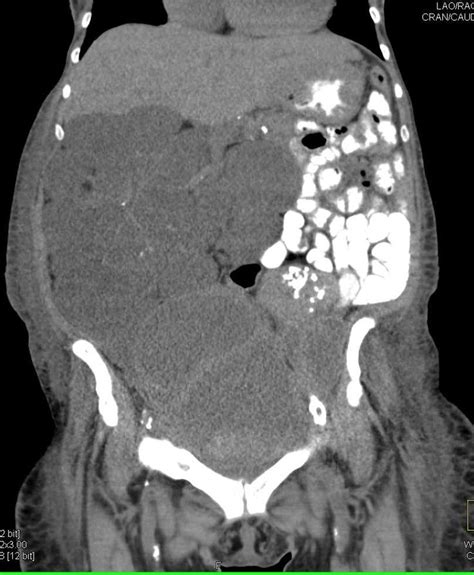

Diagnosing Pseudomyxoma Peritonei (PMP) can be a bit of a detective game, guys, because, as we’ve mentioned, the symptoms can be pretty sneaky. When you go to the doctor with persistent bloating, abdominal discomfort, or changes in bowel habits, they’ll likely start with a thorough physical examination. They’ll be feeling your abdomen for any swelling, masses, or tenderness. Then, they’ll usually move on to imaging tests. The most common and effective imaging tool for PMP is a CT scan (computed tomography) of the abdomen and pelvis. This scan can often show the characteristic mucinous ascites – that’s the fancy medical term for the jelly-like fluid filling the abdominal cavity. It can also help identify the primary tumor, if it’s still visible, and see how widespread the disease is. Sometimes, an MRI (magnetic resonance imaging) might be used, which can provide even more detailed images of soft tissues. Blood tests are also usually done, but they typically don’t provide a definitive diagnosis for PMP . They can help rule out other conditions and check your overall health. In some cases, a procedure called diagnostic laparoscopy might be performed. This is a minimally invasive surgery where a small camera is inserted into the abdomen through tiny incisions. This allows the surgeon to directly visualize the abdominal cavity, assess the extent of the PMP , and take biopsies of any suspicious areas. Biopsy results are crucial because they confirm the presence of the specific type of mucinous tumor cells characteristic of PMP . The definitive diagnosis is usually made by a pathologist examining tissue samples under a microscope. It’s important to remember that sometimes, PMP is discovered incidentally during surgery for another condition, like an appendectomy, if the appendix is found to be ruptured or abnormal. Because PMP is rare, it’s essential to be seen by specialists who have experience with this condition. They’ll know what to look for on the scans and how to interpret the findings. The diagnostic process can sometimes take time, and it’s natural to feel anxious, but getting an accurate diagnosis is the critical first step towards effective treatment.